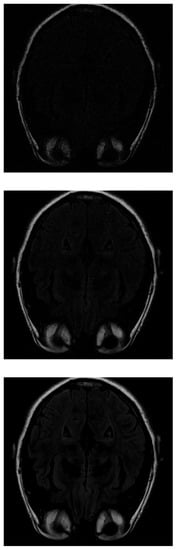

In the IRLS reconstruction, only the shape of the head and the orbits are detected in the first measurements, while the white matter is not distinguishable (Figure 5 top). When 70% of the data is available (Figure 5 middle), the white matter can be distinguished but with little intensity. When the intensity of the orbits increases, the effect of the artifact begins to be noticed. If the algorithm is run with all available data (Figure 5 bottom), the edge resolution is increased, but white matter signal intensity is lost. That makes their identification more difficult.

Figure 5. Reconstruction of the image in Figure 3 using IRLS with 30 % (top), 70 % (middile) and 100 % (bottom) of taken measurements.

Mathematics 11 03573 g005